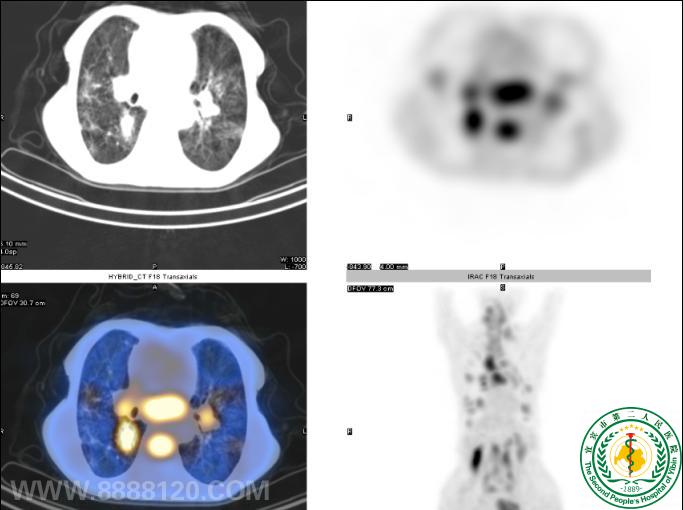

“鹰眼PET/CT”发现结肠Ca术后多处转移一例

“鹰眼PET/CT”发现结肠Ca术后多处转移一例6506